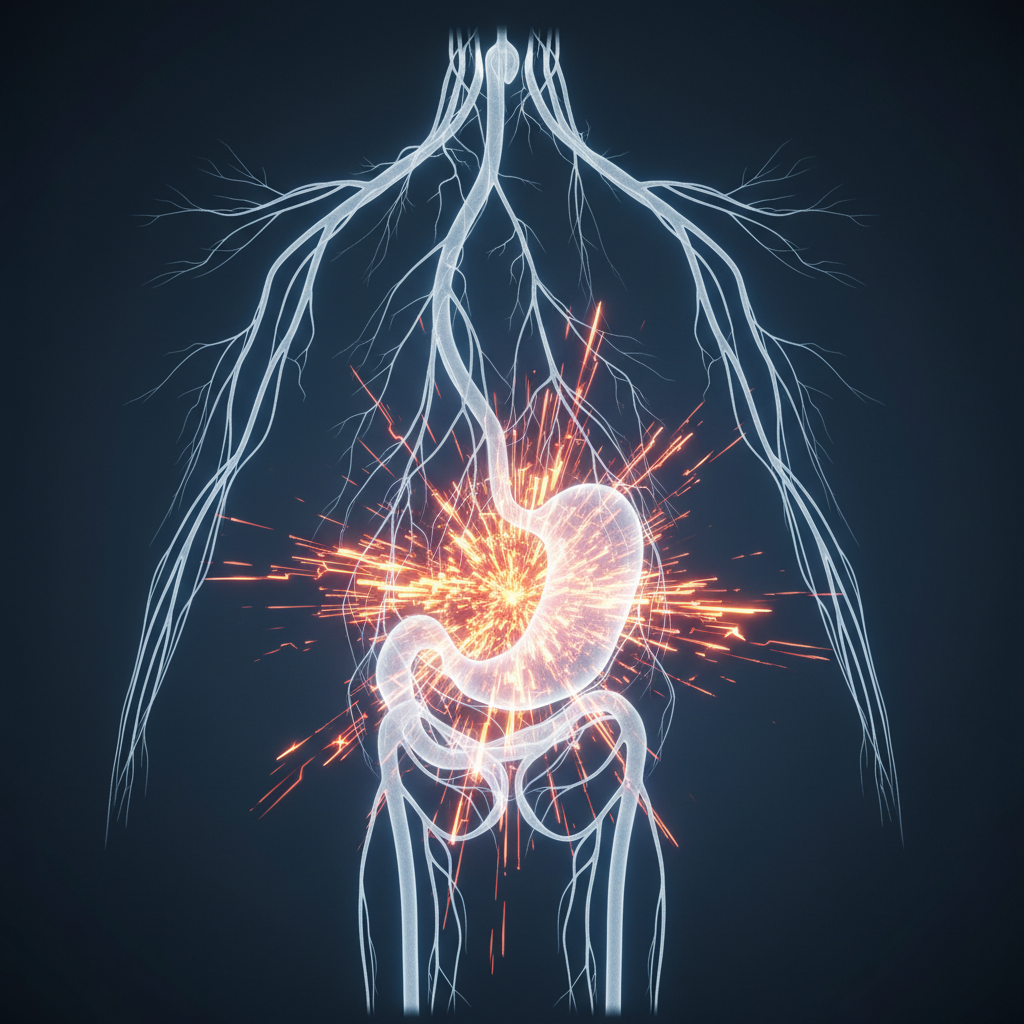

1. 소화기계 문제

위식도 역류 질환, 위염, 식도염 등 소화기 계통의 문제가 횡격막이나 미주신경을 자극하여 딸꾹질을 유발할 수 있어요. 속 쓰림이나 소화 불량과 함께 딸꾹질이 계속된다면 의심해 볼 필요가 있습니다.